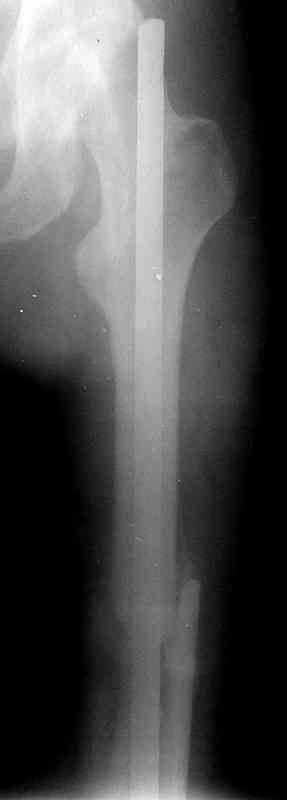

по его наружной поверхности послеоперационный рубец - рана зажила первичным натяжением. При измерении длины бедер обнаружено укорочение левого бедра на 4,5 см. На рентгенограммах этого бедра: ось конечности правильная, отмечается захождение основных костных фрагментов по длине, проксимальный конец штифта выступает слишком медиально и высоко относительно большого вертела, периостальная мозоль незначительна.22.12 - через 6 месяцев после операции, произведенной в ЦРБ, нами по поводу замедленно консолидирующего перелома левой бедренной кости с ее абсолютным укорочением под наркозом произведена операция: удаление штифта, закрытый блокирующий интрамедуллярный остеосинтез перелома левого бедра штифтом без рассверливания (UFN) длиной 40 см, диаметром 10 мм с блокированием только проксимальных отверстий (динамический остеосинтез). Наложен аппарат Илизарова на 4 полукольцах с целью удлинения укороченного бедра. Послеоперационное течение без особенностей. Ежедневно осуществляли дистракцию отломков на 1 мм. Через 3 недели после операции больной выпи-сан на амбулаторное лечение с продолжением дистракции отломков. В течение 1,5

месяцев дистракции укорочение левого бедра удалось полностью устранить. 22.02.00, т.е. через 2 месяца после повторного остеосинтеза, больному произведено дистальное блокирование штифта двумя винтами и демонтирован аппарат Илизарова. В течение 2 недель после операции больной ходил с помощью костылей, потом 2 недели с тростью. Опороспособность и функция оперированной конечности полностью восстановились через 4 недели после операции.

Фиксаторы удалены через 12 месяцев после операции, выполненной по поводу замедленной консолидации перелома бедра с его укорочением.